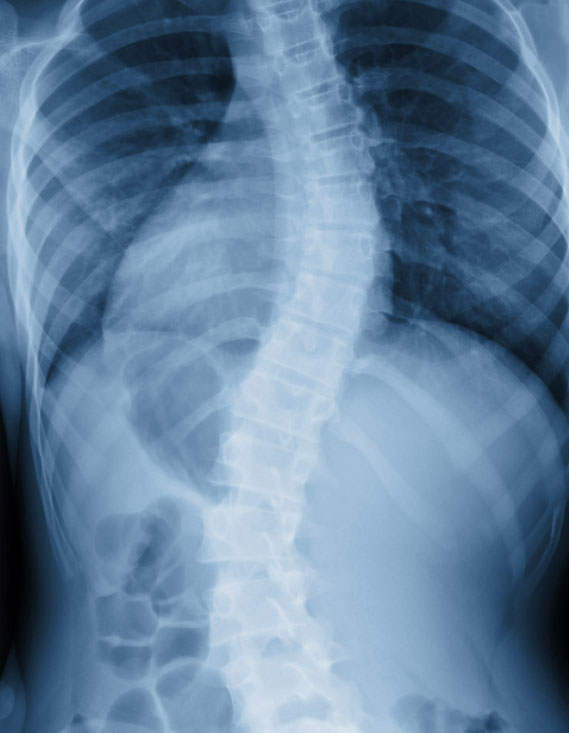

- Scoliosis is a progressive, lateral curvature of the spine. When viewed from the side, the spine should have curves. However when viewed from the back, the spine should be straight.

- Typically someone is diagnosed as having scoliosis if the curve is measured on an X-ray at 10 degrees or more combined with rotation of the vertebrae/spine. This measurement is known as the cobb angle of the scoliosis curve.